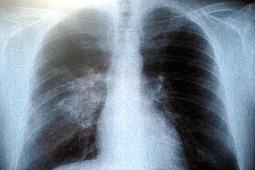

Wirus podobny do tych, które wywołują SARS i przeziębienia, pojawił się w zeszłym roku. Na całym świecie zmarło 23 z 44 zarażonych. W większości były to osoby, które podróżowały na Bliski Wschód. Zmarły we wtorek 65-latek niedawno wrócił z Dubaju. Wirus powoduje zapalenie płuc i czasami niewydolność wielonarządową.